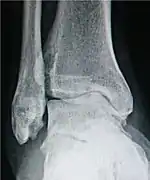

- For the ankle, the Kellgren-Lawrence scale, as described for the hip, has been recommended.[16] The distances between the bones in the ankle are normally as follows:[17]

- Talus - medial malleolus : 1.70 ± 0.13 mm

- Talus - tibial plafond: 2.04 ± 0.29 mm

- Talus - lateral malleolus: 2.13 ± 0.20 mm